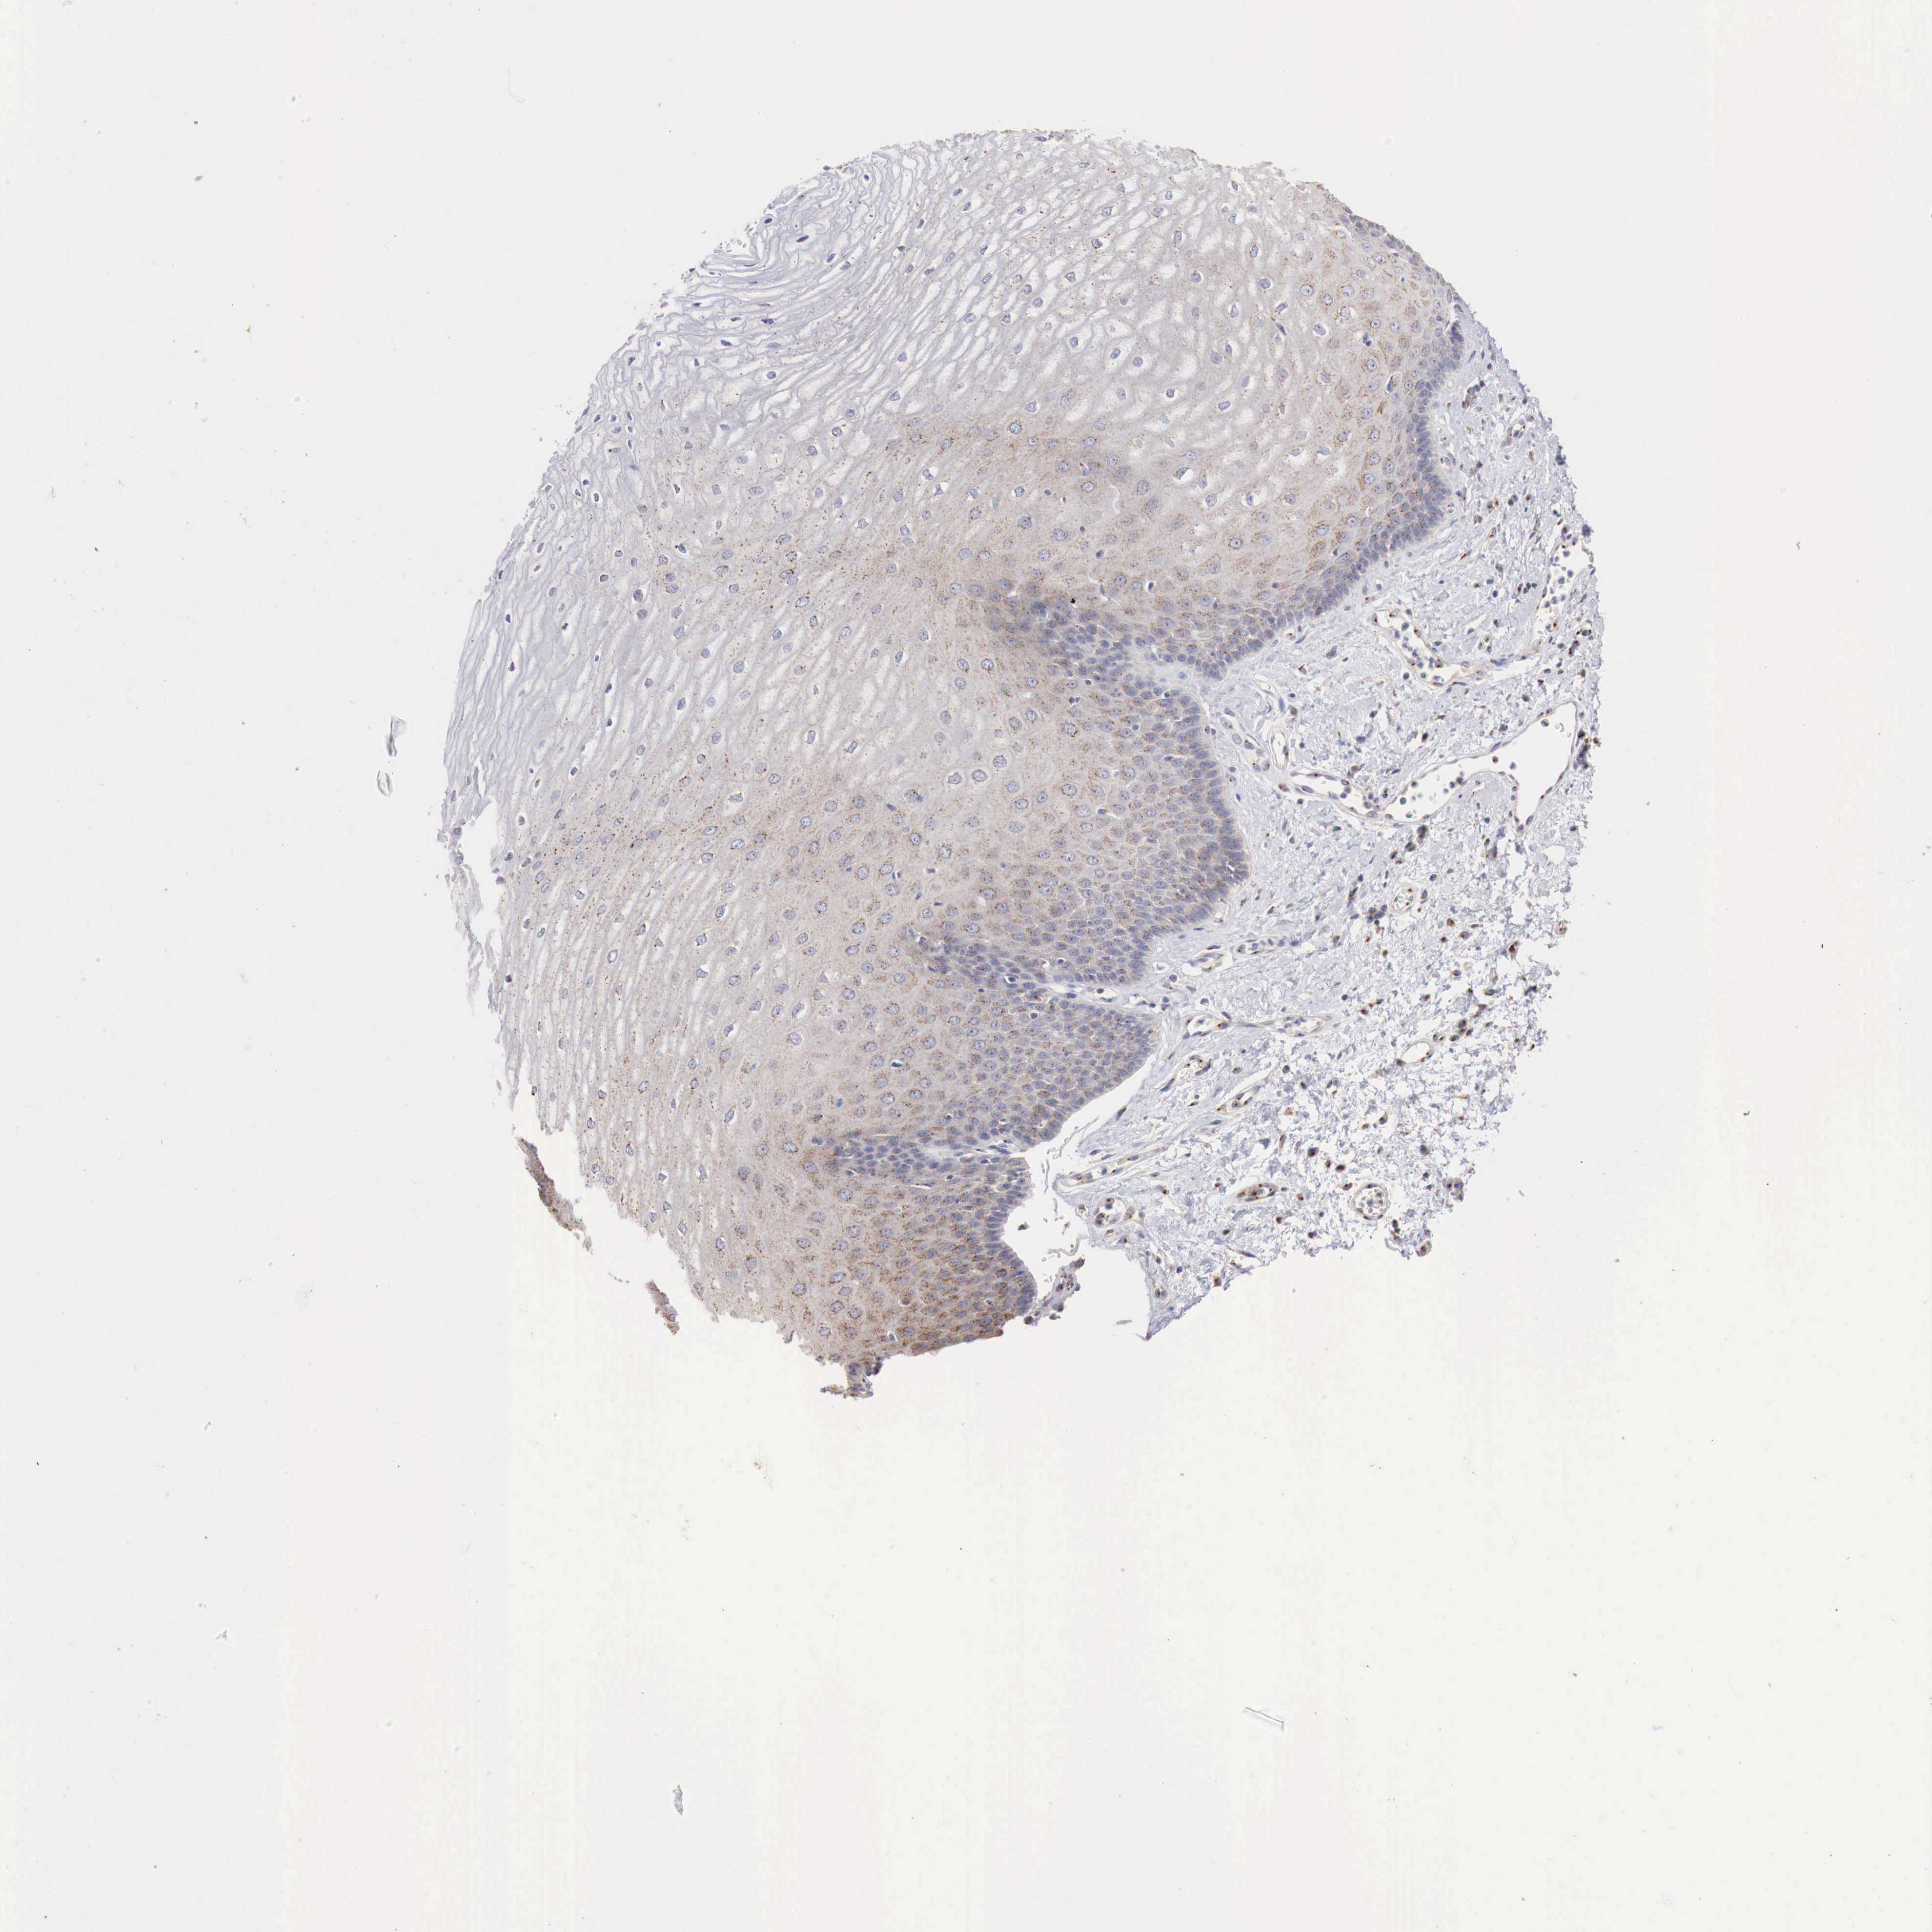

ESOPHAGUS - Antibody stainingi

Antibody staining in the annotated cell types in the current human tissue is reported as not detected, low, medium, or high, based on conventional immunohistochemistry profiling in selected tissues. This score is based on the combination of the staining intensity and fraction of stained cells.

Each image is clickable and will lead to virtual microscopy that enables deeper exploration of all samples and also displays staining intensity scores, fraction scores and subcellular localization as well as patient and tissue information for each sample.

Antibody HPA000175

Squamous epithelial cells Medium